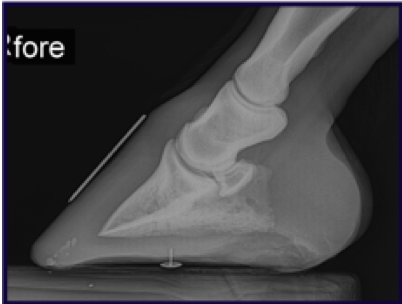

- Navicular and “Sinker” Recovery